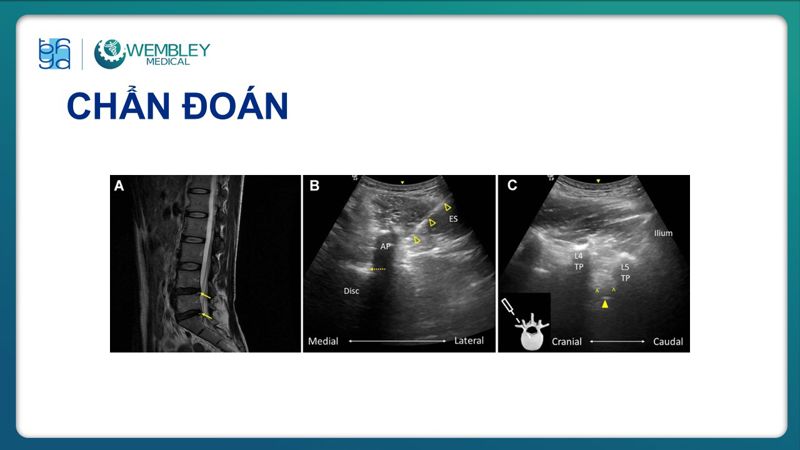

Huyết tương giàu tiểu cầu (PRP) ngày càng được ứng dụng rộng rãi trong điều trị đau mạn tính nhờ khả năng hỗ trợ tái tạo mô và giảm viêm hiệu quả.

Trong bài báo cáo tại Hội thảo VAI TRÒ CỦA HUYẾT TƯƠNG GIÀU TIỂU CẦU TRONG ĐIỀU TRỊ BỆNH LÝ CƠ XƯƠNG KHỚP (26/07/2025), TS.BS. Lê Viết Thắng - Trưởng Đơn nguyên Điều trị đau, Khoa Ngoại Thần kinh, Bệnh viện Đại học Y Dược TP.HCM đã chia sẻ những góc nhìn chuyên môn, kinh nghiệm lâm sàng và đánh giá thực tiễn về hiệu quả của PRP trong điều trị đau mạn tính, góp phần làm rõ vai trò của PRP trong chiến lược điều trị hiện đại, an toàn và cá thể hóa cho người bệnh.